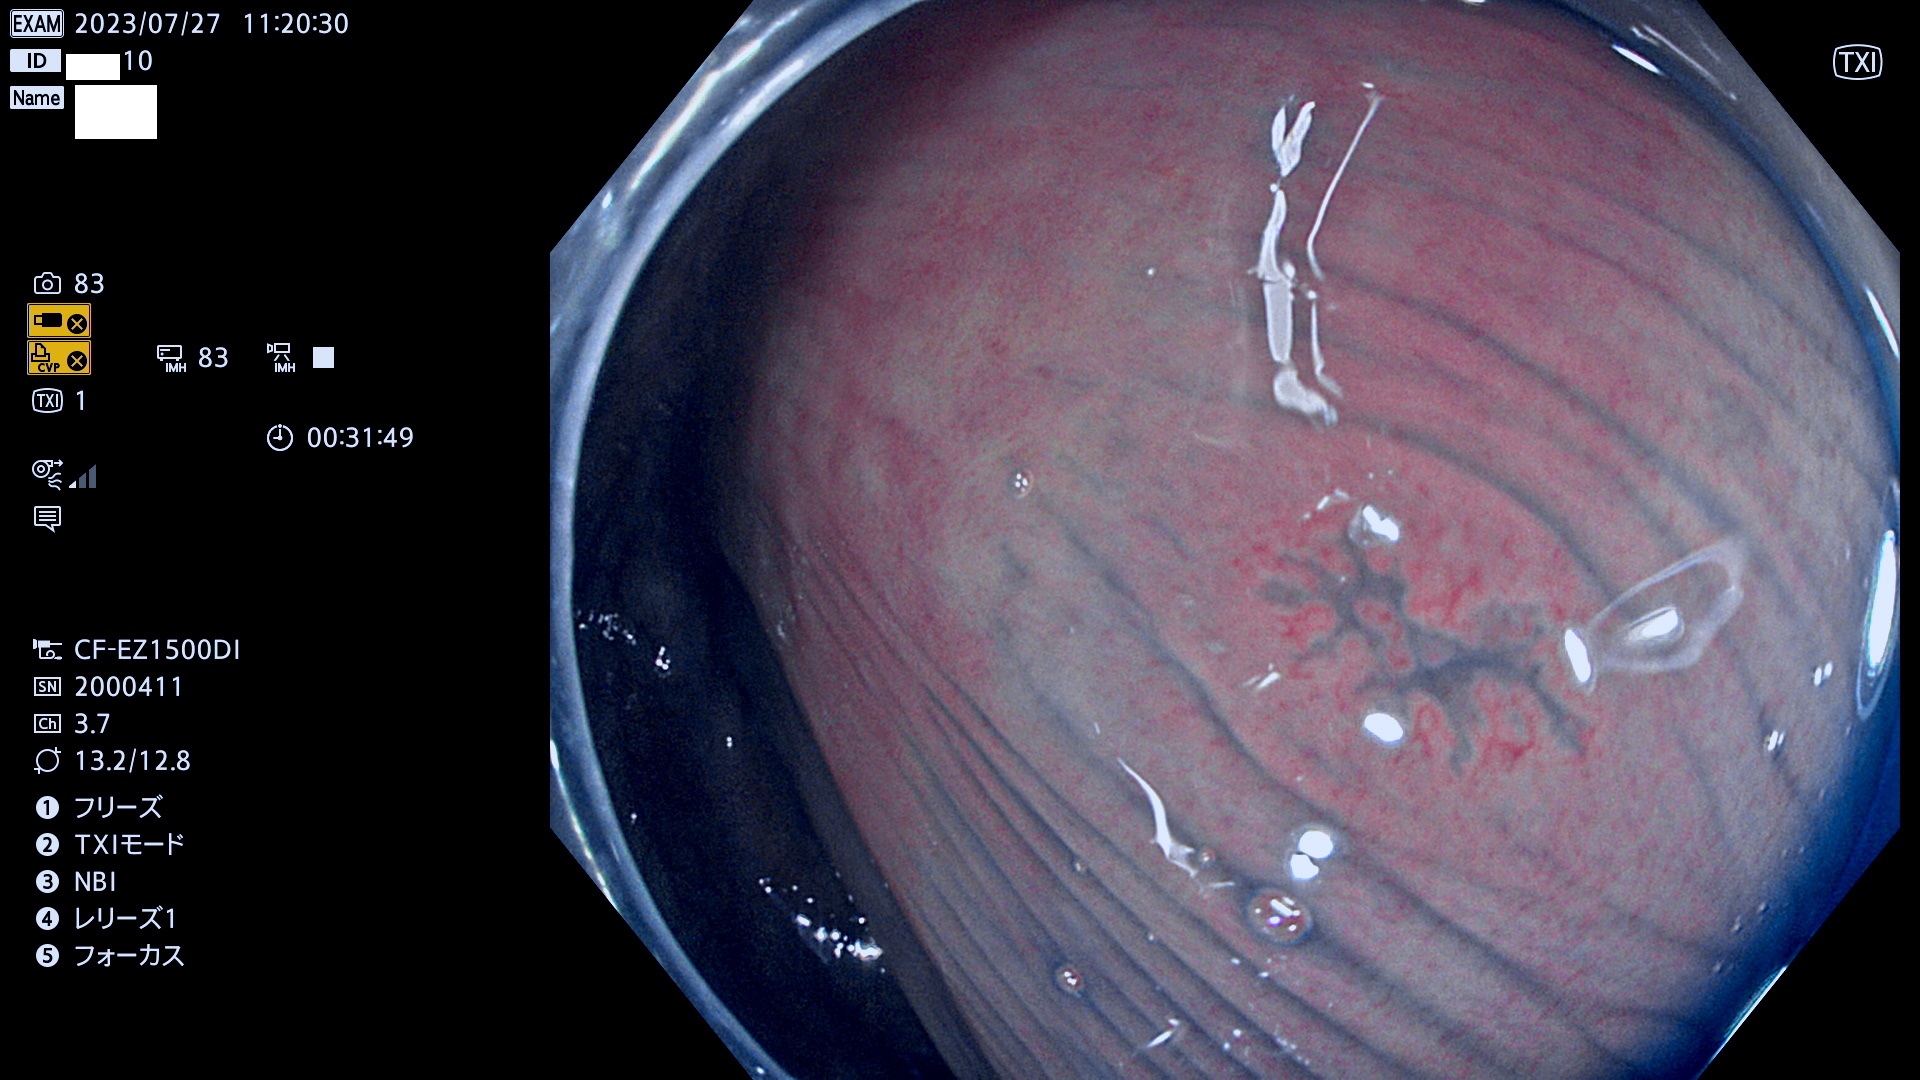

表面型腺腫(Flat Adenoma)の中で、完全に平坦な物をUb、陥凹している物をUcと呼びます。平坦隆起型(Ua)よりも、発見が難しく危険な病変です。このタイプは「内視鏡後・大腸癌の重要犯人」であり、この発見率は「腺腫発見率」よりも、重要な意味があります。

専門的)何故、陥凹していると危険? 癌遺伝子の変異が蓄積すると細胞分裂が盛んになり隆起するのでは?と通常は思われるでしょう。しかし実際は逆です。これは2022年の記事にある「細胞はストレスに直面したら細胞分裂を止める(細胞老化に入り休眠する)という生命の基本的現象」によるものです(Oncogene Stress)。細胞老化を起こすのが癌抑制遺伝子で、この安全装置(ブレーキ)が壊れると癌になります(休眠からの覚醒)。ですから陥凹は「まだ癌では無いが癌化の直前」を意味します。特に「小サイズなのに陥凹している」病変は短期間に腫瘍進化(⇒2021年記事)が起きたことを意味します(=ゲノム不安定性

毎週の検査(木・金・土・日)に発見されたUb、Uc型・腺腫を、その週の日曜の夜にUPし1週間、提示します。

抽出の対象期間 2023年7月27日(木)〜7月30(日)の4日間(48件の検査)11件